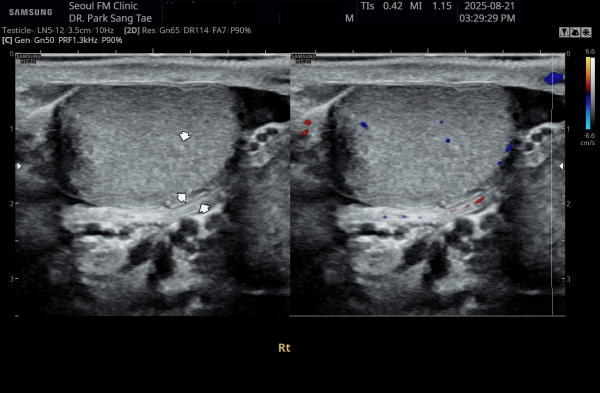

약 8개월 전 전립선과 전립선관,사정관,사정관입구,정낭 그리고 정관의 표적 치료전 우측 정관과 고환의 순환장애로

고환의 섬유화가 관찰되는 초음파 사진입니다.

This ultrasound image, taken about 8 months ago before starting targeted treatment of the prostate, prostatic ducts, ejaculatory ducts, seminal vesicles, and vas deferens, shows poor circulation in the right testicle. Due to this circulation problem, some fibrosis (scarring) of the testicle can be observed.